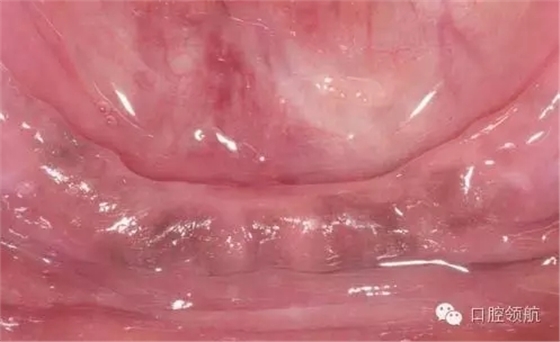

初診時(shí),口內(nèi)所見(圖1),曲面斷層片顯示(圖2),患者植入?yún)^(qū)骨量不足,前庭溝深度不足,附著齦的量不足。

圖1 初診時(shí)口內(nèi)所見。